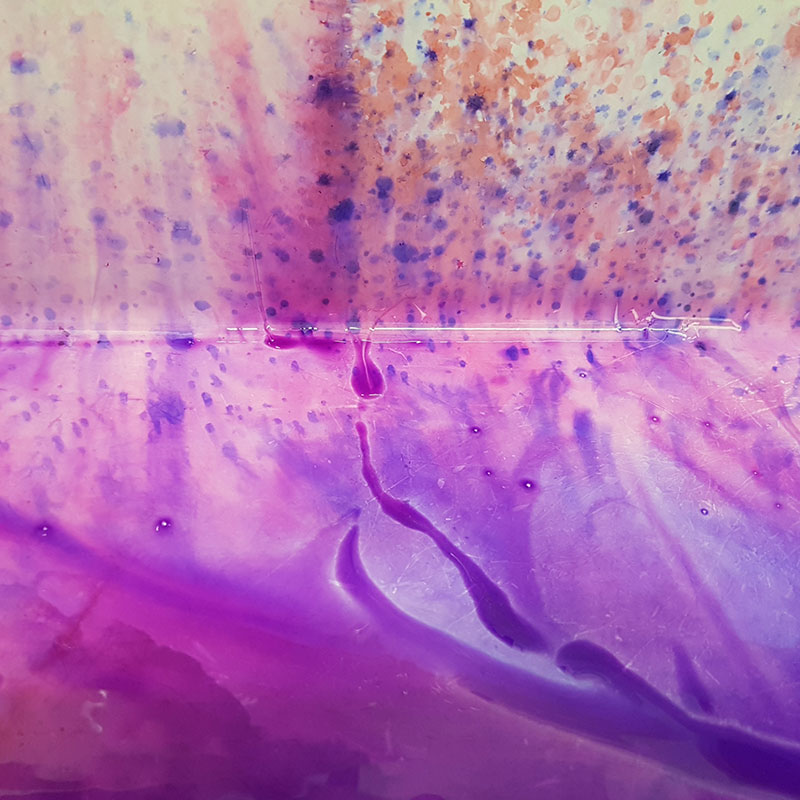

Waters of Pathology

Gink Yang

Future Industries Institute

Pathological assessment of biological samples often requires the use of Haematoxylin and Eosin (H&E) staining. My own research, nonetheless requires this simple procedure to assess the severity and progression of tumours and wounds. This simple yet crucial experimental process is often overshadowed by other complicated procedures. Here, the elegant and velvety watercolours of H&E is captured as the experimental procedures are being carried out. The image itself represents the unsung heroes in our scientific world

as well as in our society.